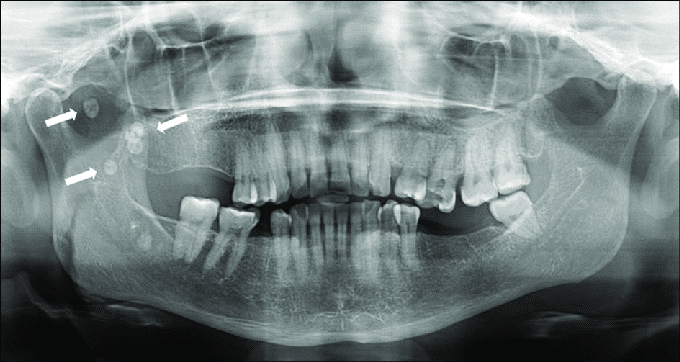

6. (Select ONE correct answer)

What is the most likely entity indicated by arrows?